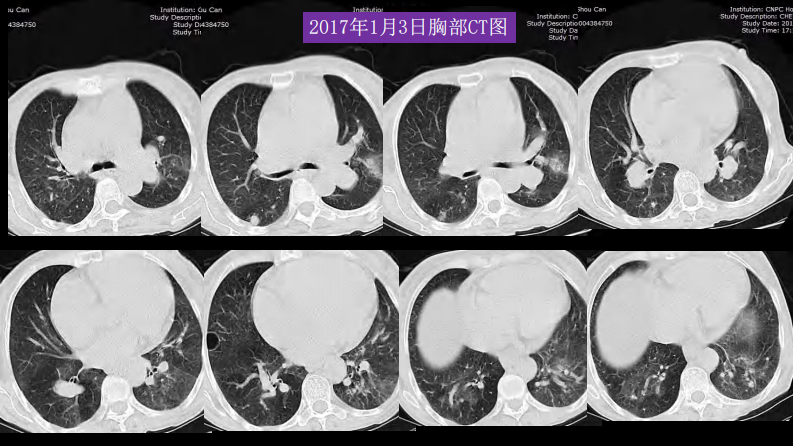

胸部影像解读:心肺一体性疾病.pdf